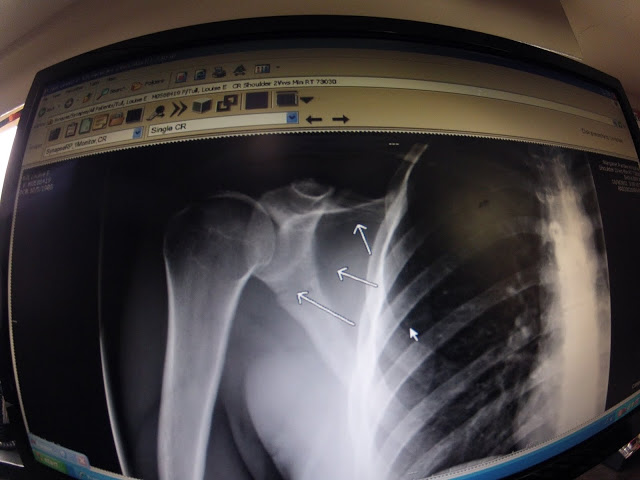

I was taken to the hospital and checked over and when the xray results came back the Dr. Diagnosed a fracture on my scapular. I was pretty drugged up in the hospital so was feeling pretty positive and not too bad about the whole thing. But when I got home that night the realisation of what had happened hit me.

It takes a lot of force and a hard hit to break the scapular so my body was in quite a bit of shock. But for me, I know my body will heal. The fortunate thing about bone injuries is that they heal back to 100% in 6-8weeks. The harder part in my mind is the fact that I let this happen, I messed up and made the mistake which led to this accident. I should have got out of my boat and scouted the rapid again, taken it more seriously and been sure of my line. Any new river I have paddled this year I have given full respect to and always made sure I charge my lines, because I know you have to. What scares me is that I messed up the other day. Something in my brain was not working or making me stop and think about what I was doing, I was not sure of the line and I still went. Human error maybe but this is something I could have avoided. I know I could have because I owned that rapid just a couple of days earlier. It was not a question of could I do it or not, I had already done it well. Just mentally I was not strong and this reflected in my pathetic strokes and hesitation. My confidence in my ability is low right now and I feel super gutted. Kayaking class 4/5 requires confidence and I feel like I let myself down the other day.